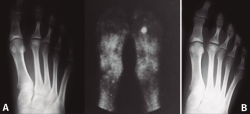

Las necrosis asépticas aparecen en aquellos puntos de nuestro aparato locomotor sometidos a importantes solicitaciones mecánicas, sea por microtraumatismos o por sobrecarga estructural. En el caso de la enfermedad de Freiberg, diversos autores(2,10,11,12) apoyan esta teoría que nosotros compartimos, ya que hemos visto muchos casos de afectación del segundo metatarsiano acompañando una insuficiencia del primer radio, sea por un hallux valgus o por un primer metatarsiano corto (Figura 2). En nuestro estudio a largo plazo sobre la enfermedad de Freiberg(13), sobre 16 pies operados, 12 padecían la sobrecarga mecánica.

Figura 2. Etiología mecánica. La enfermedad de Freiberg se asocia frecuentemente a una insuficiencia del primer radio.

Figura 5. Tratamiento conservador. Paciente tratada con plantilla de descarga. A: imágenes al inicio del tratamiento; B: 2 años más tarde, mínima afectación articular.

En las fases iniciales (estadios 1 y 2 de Smillie) en las que, tal como se ha comentado, las molestias del paciente son inexistentes o leves, están indicadas las plantillas ortopédicas de descarga de la cabeza metatarsal afecta, los antiinflamatorios no esteroideos (AINE) y la electroterapia antiinflamatoria durante la crisis de dolor. Se recomienda al paciente disminuir la práctica deportiva de impacto(11,17). Con ello se consigue que, cuando se finaliza la fase de reparación, la deformidad sea la menor posible (Figura 5).